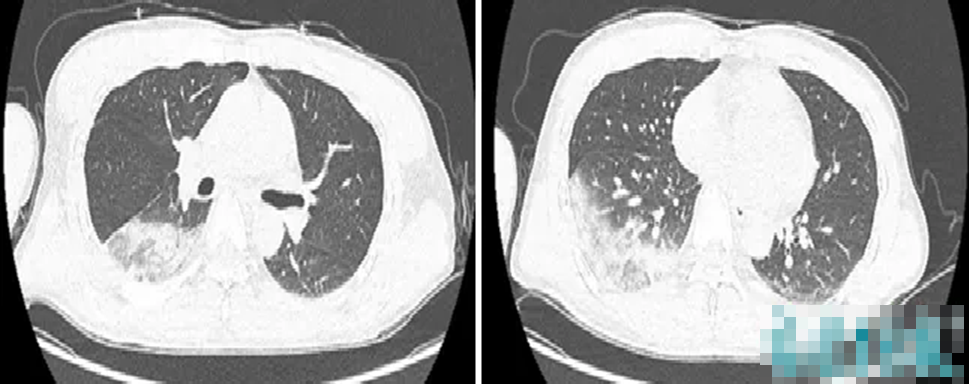

Kết quả kiểm tra cho thấy hai thuỳ phổi dưới đã viêm, chức năng gan thận đều tổn thương, chỉ số viêm tăng cao bất thường.

Khi bác sĩ truy lại tiền sử sinh hoạt, nghe tới chuyện “nuôi chim trong túi áo”, tổ chuyên môn lập tức nghi ngờ anh Lâm mắc bệnh Chlamydia psittaci (sốt vẹt).

Xét nghiệm chuyên sâu và giải trình tự gene mầm bệnh đã xác nhận đúng là nhiễm Chlamydia psittaci.